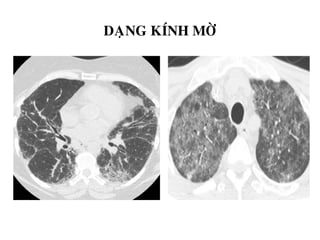

DAÏNG KÍNH MÔØ

-Ñaùm môø nheï, khoâng xoùa môø maïch maùu trong vuøng

toån thöông.

-Phuø phoåi, vieâm phoåi, xuaát huyeát phoåi…